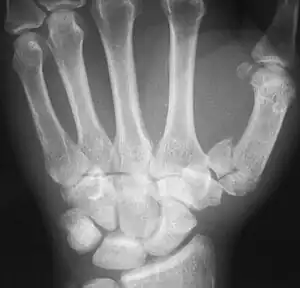

| Rolando fracture | Silvio Rolando | intra articular comminuted fracture of base of first metacarpal | axial load along the metacarpal causing splitting of the proximal articular surface | Rolando's fracture Archived 2020-09-18 at the Wayback Machine at Wheeless' Textbook of Orthopaedics online | ![]() |